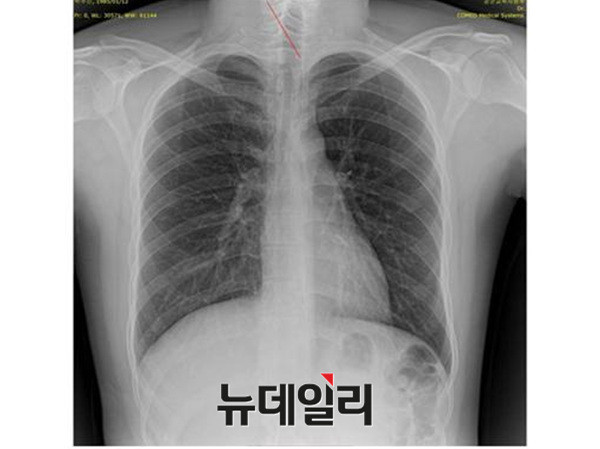

2011년 박주신씨에 대한 병역비리 의혹이 처음 불거진 뒤 지금까지 박주신씨의 신체를 촬영한 것으로 알려진 엑스레이는 모두 3개가 있다.이 가운데 언론을 통해 널리 알려진 자생병원 엑스레이(촬영일자 2011년 12월 9일)는, 박주신씨 본인이 아닌 제3자의 신체를 촬영한, 이른바 ‘대리신검자 엑스레이’라는 의심을 받고 있다.

- ▲ 박주신씨 명의의 자생병원 엑스레이. ⓒ 뉴데일리DB

반면 지난해 12월부터 시작된 양승오 박사 등 시민 7명에 대한 공직선거법 위한 공판을 통해 새롭게 밝혀진, 박주신씨의 ‘공군훈련소 입소 당시 엑스레이’(촬영일자 2011년 8월 30일, 이하 공군 엑스레이)와, 주신씨가 ‘비자발급을 위해 촬영한 세브란스병원 엑스레이’(촬영일자 2014년 7월 31일, 이하 비자발급용 엑스레이)는 각각 박주신씨 본인의 신체를 촬영한 것으로 받아들여지고 있다.

- ▲ 박주신씨 공군훈련소 입소 당시 촬영된 엑스레이. ⓒ 뉴데일리DB

- ▲ 박주신씨가 지난해 7월 비자발급을 위해 촬영한 엑스레이. ⓒ 뉴데일리DB

이들 세 개의 엑스레이는 모두 박주신씨의 신체를 촬영한 것으로 알려져 있기 때문에, 이들 엑스레이에 대한 판독결과 피사체를 동일인으로 볼 수 없는 유의미한 차이점이 발견된다면, 이는 박주신씨의 대리신검 혹은 영상자료 바꿔치기 의혹을 뒷받침하는 결정적 단서가 된다.

세계적 권위를 인정받은 영상의학 전문의인 양승오 박사(동남권원자력의학원 암센터 핵의학과 주임과장)와 치과의사 김우현씨 등 박주신씨 병역비리 의혹을 주장해 온 시민들은, 위에서 언급한 세 개의 엑스레이에 대한 비교 판독 결과, 이들 엑스레이를 같은 사람의 것으로 볼 수 없는 차이점을 발견하고 이를 재판부에 증거자료로 제출했다.

‘석회화’와 ‘극상돌기’

‘석회화’란 나이가 들어 뼈에 발생하는 퇴행성 증상의 하나로 질병이라고 볼 수는 없지만 한 번 생기면 없어지지 않으며, X-Ray를 통해 확인할 수 있는 것으로 알려졌다.

-

- ▲ ▲박주신의 자생병원 X-Ray(왼쪽)과 공군 X-Ray(오른쪽). 자생병원의 엑스레이에서는 오른쪽 제1늑골부위에 '석회화'현상이 보이지만 공군엑스레이에선 보이지 않는다. ⓒ 뉴데일리DB

박주신씨의 자생병원 X-Ray를 보면, 오른쪽 제1 늑골부위에 ‘석회화’ 현상이 나타난다. 그러나 주신씨가 공군 입대 당시 찍은 X-Ray에는 이런 모습이 전혀 보이지 않는다.

이런 차이에 대해 양승오 박사의 변호인인 차기환 변호사 등은 "각각의 X-Ray를 찍은 사람이 동일인이 아니라는 것을 입증한다"고 설명했다.

‘극상돌기’의 경우에도 차이점은 명확히 드러난다.

변호인 측은 “공군에서 찍은 엑스레이와 비자발급을 위해 찍은 엑스레이에서는 피사체의 제 1흉추 극상돌기가 오른쪽으로 휘어있지만, 자생병원에서 찍은 영상에서는 정방향으로 나온다”며, “박주신씨가 공군에 입대해 찍은 엑스레이와 세브란스 공개신검에서 나타난 피사체의 의학적 차이가 명확해 동일인이라고 인정할 수 없다”고 지적했다.

우리가 흔히 등을 만지면, 가운데 뾰족하게 솟아난 부분이 바로 ‘극상돌기’다.

흉추를 비롯해 모든 척추에 존재하며, 흉추에 외상이나 수술, 질병 등이 없었던 근접한 기간 동안 촬영된 엑스레이에서 극상돌기의 형태가 명확하게 다를 경우, 다른 개체라고 판단할 의학적 근거가 된다.